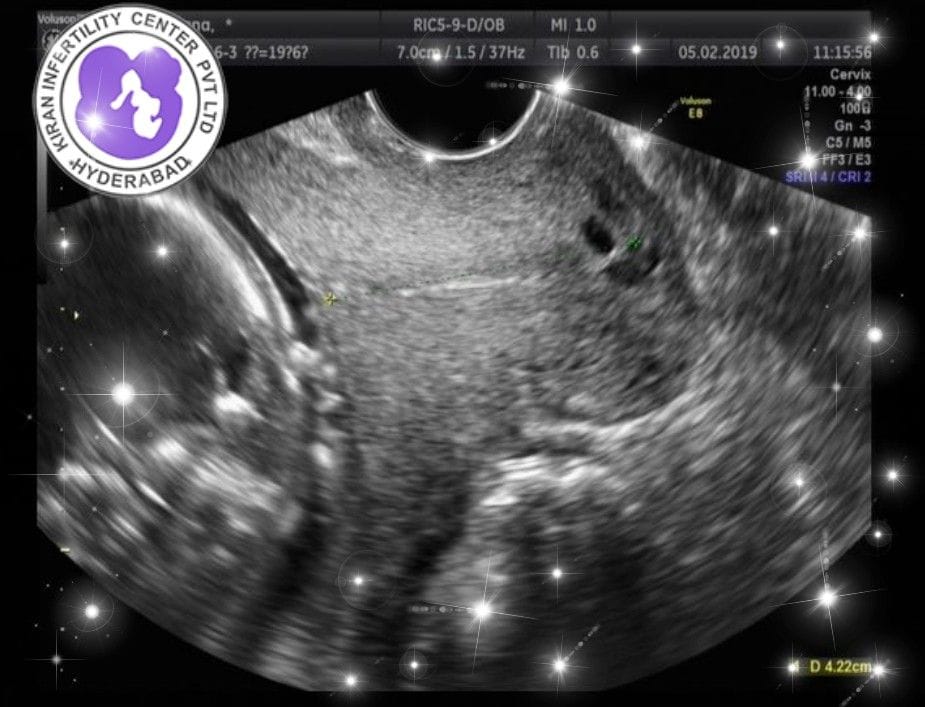

We are very happy and excited for our Intended Parents G&S, their surrogate mother currently 20 weeks pregnant and doing great!